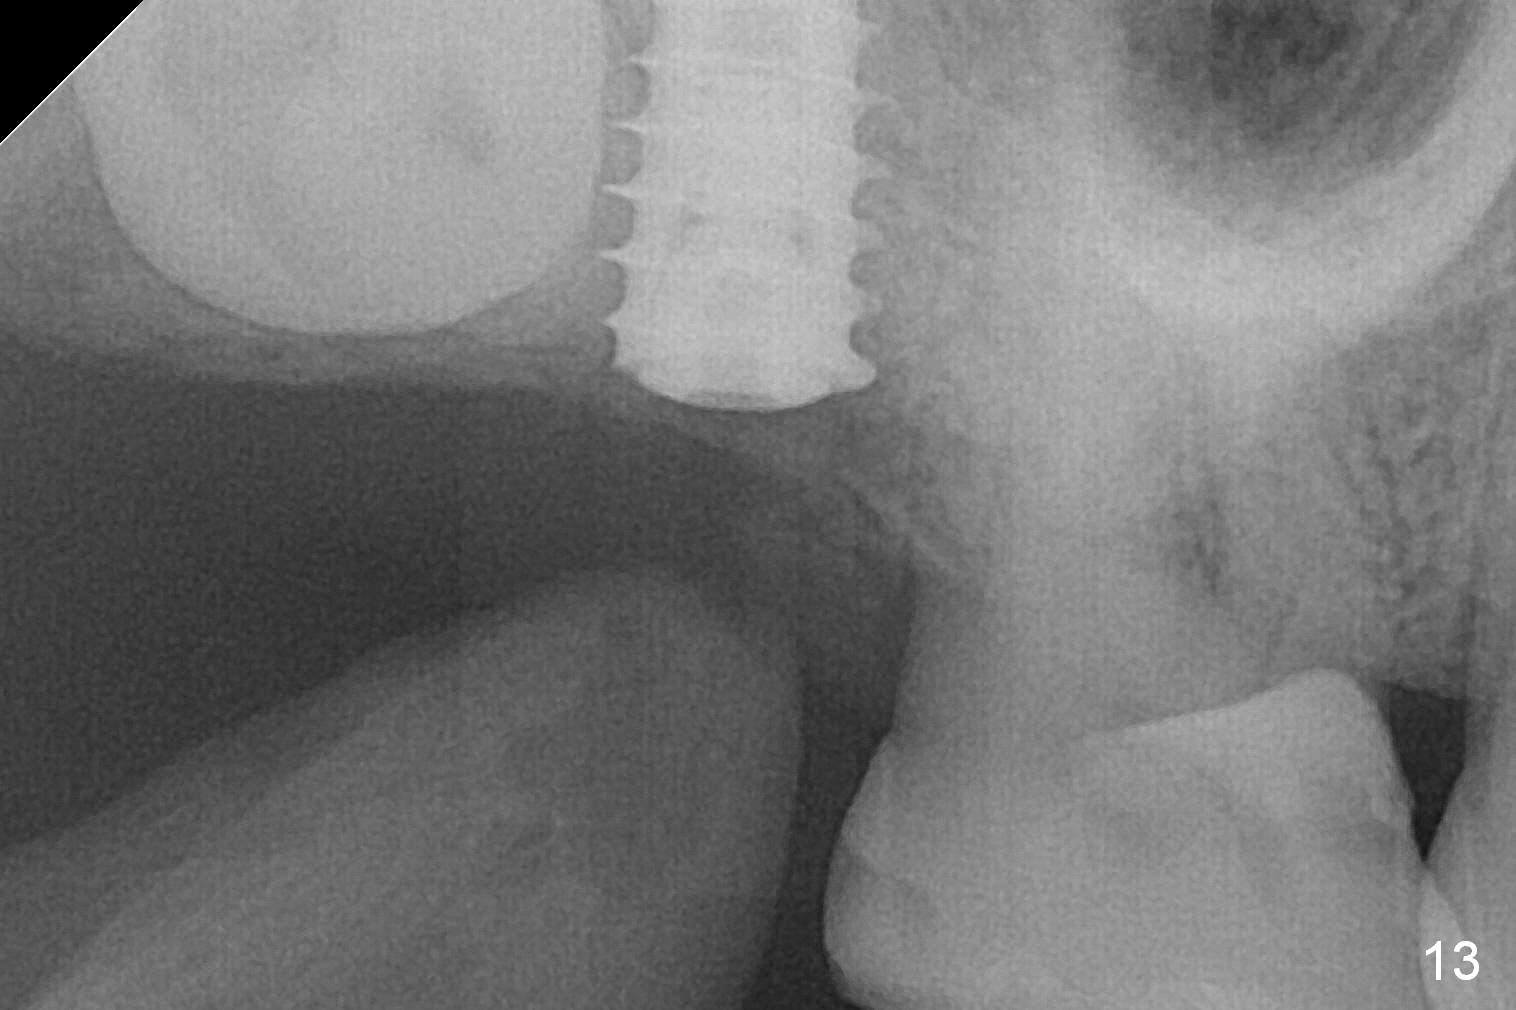

In fact, the implant is reversely torqued (1 month postop) and ~ 2 mm more coronally. It becomes looser. A healing screw is placed. With insertion of collagen plug, sutures are placed. Five days postop, the wound appears to be healing with sutures being dissolved. Four months later (5 months post placement), the patient returns asymptomatic. The wound heals. The implant appears to have osteointegrated and is at the crestal level (Fig.13,14). At uncover, the implant is found unstable; a healing abutment is placed. The implant is stable 8 months postop with apparently no gap between the bone and threads (Fig.15, as compared to Fig.13).